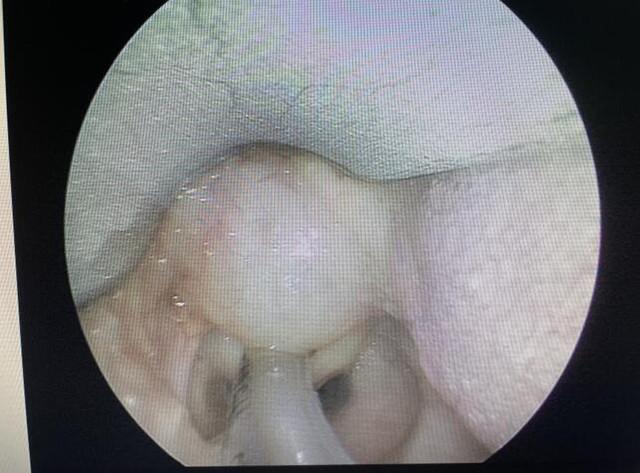

文章插图

肿瘤切除后喉部解剖回归正常